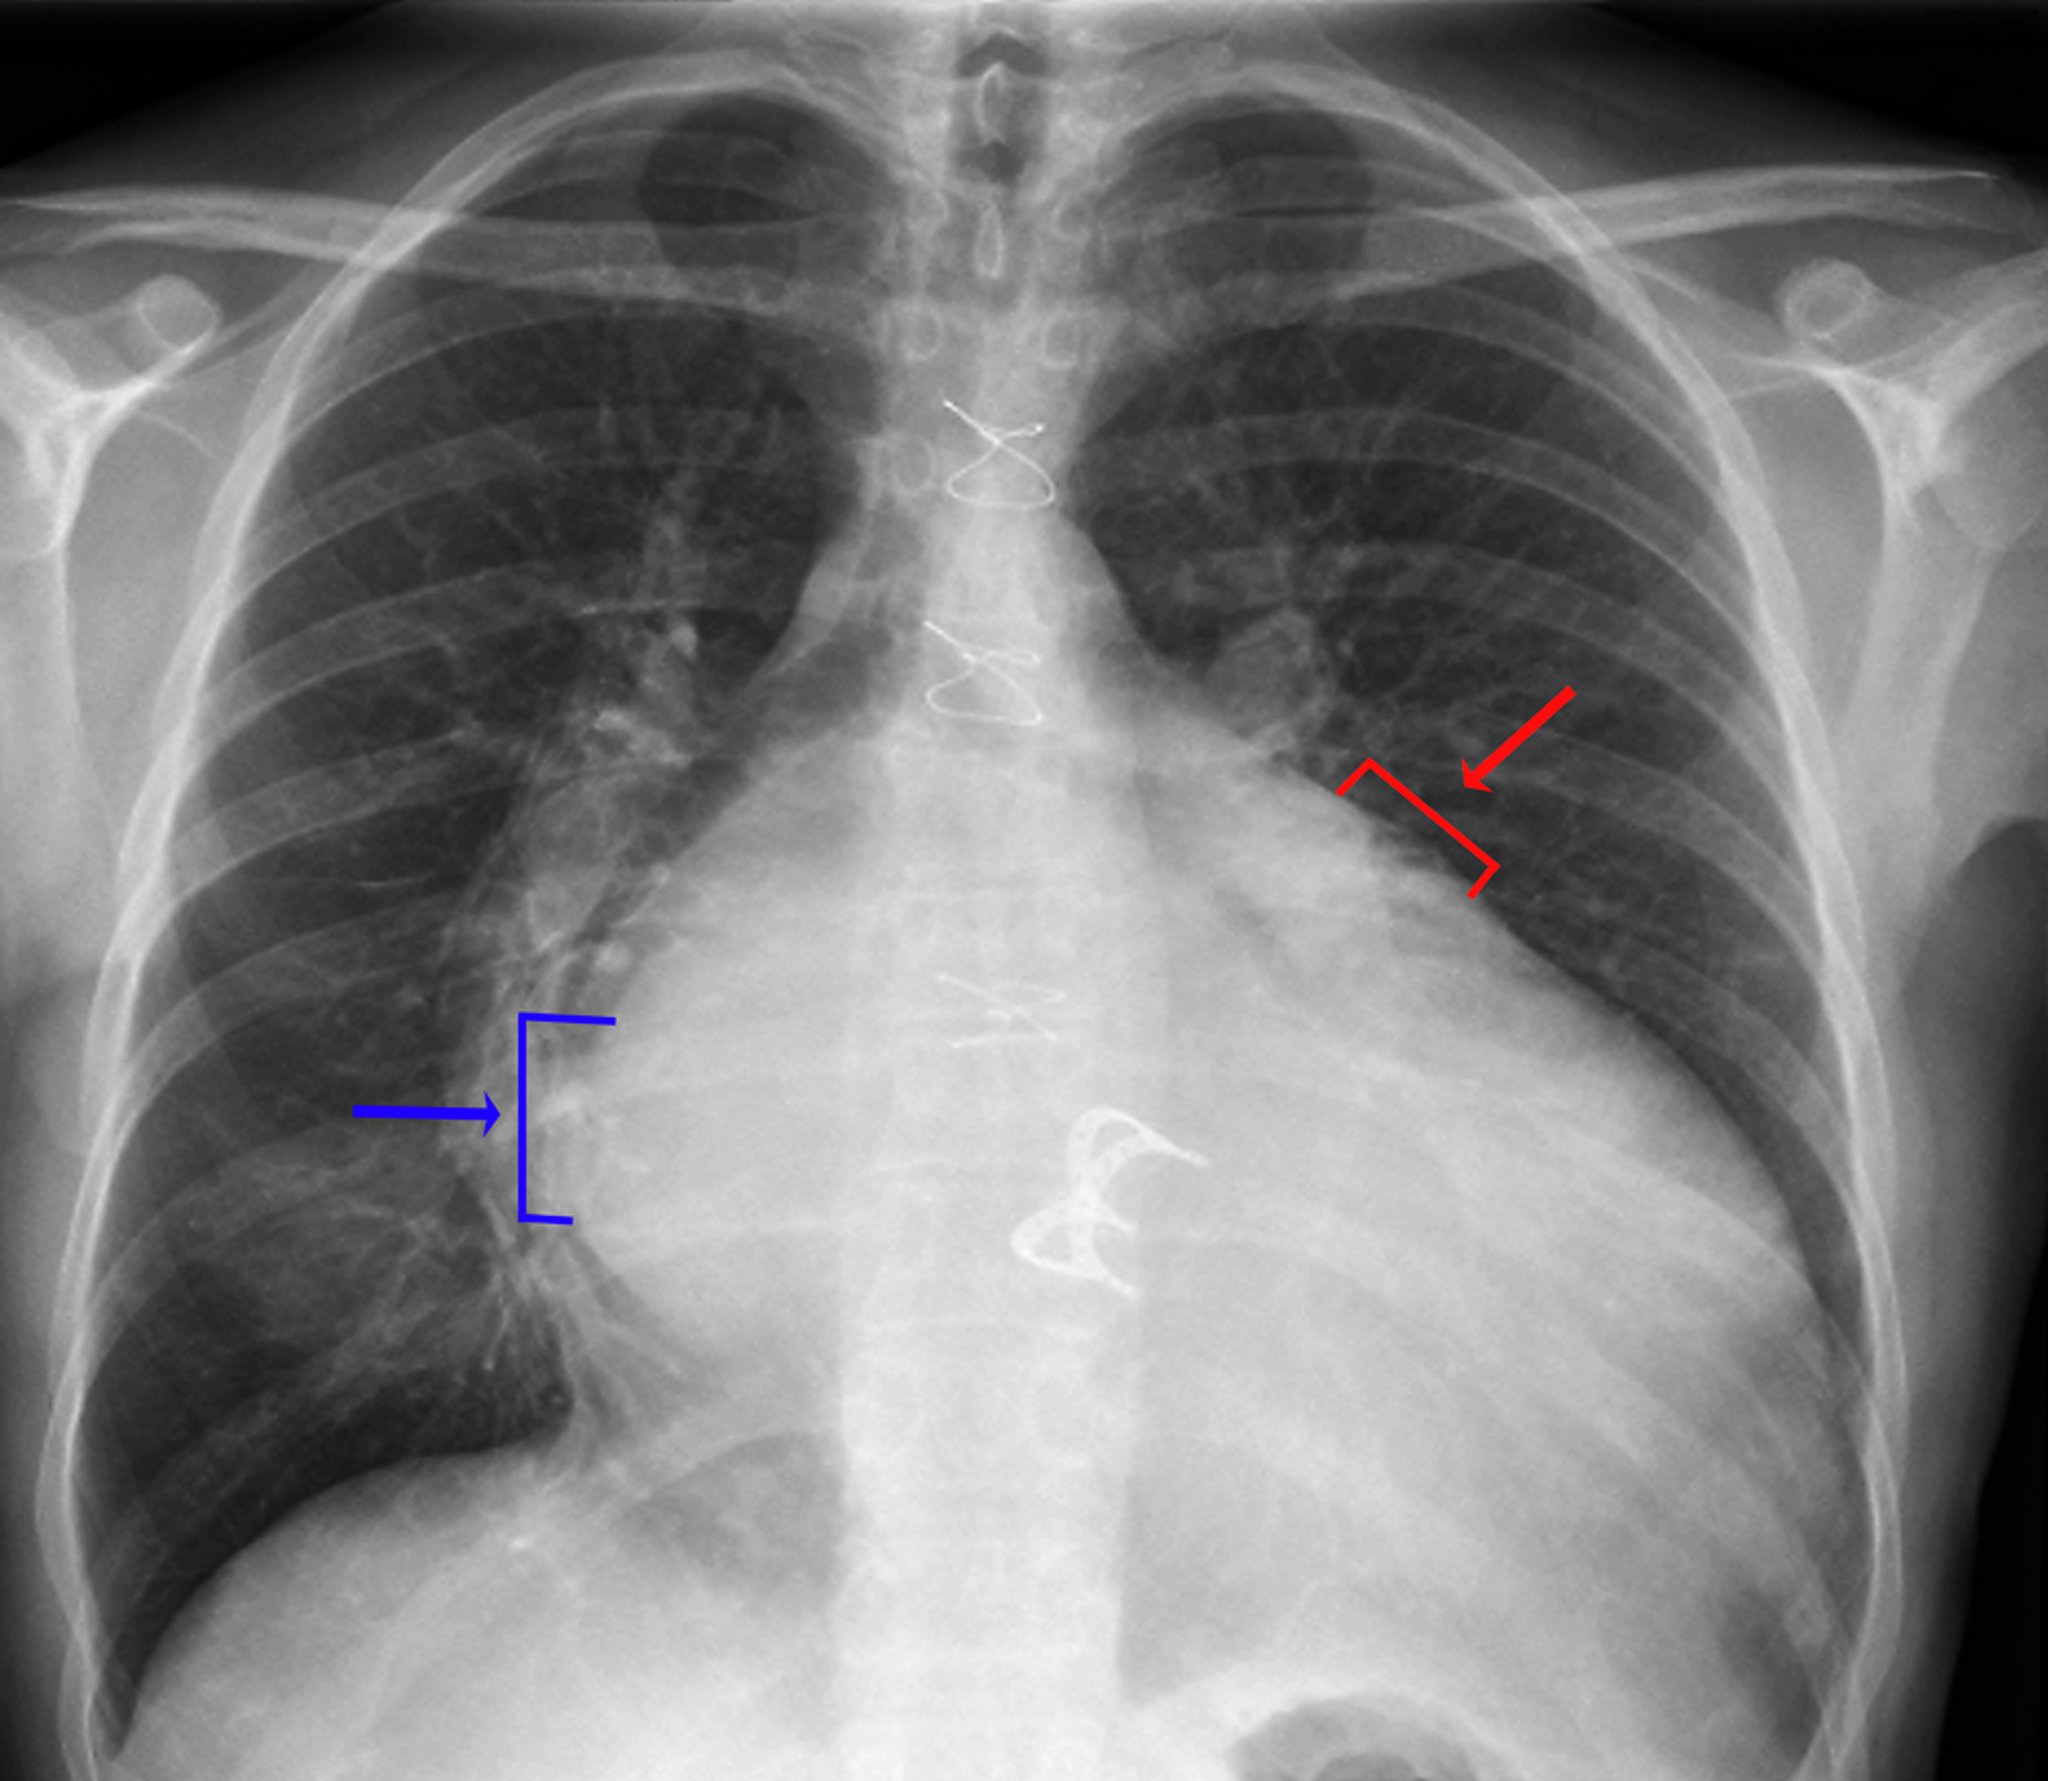

Chest Radiograph (Prosthetic Heart Valve)

Signs of left atrial enlargement include a visible density of the left atrium in the right hemithorax (blue arrow, double-density sign), increased (> 7 cm) distance between the left atrial edge in the right hemithorax and the left mainstem bronchus, a convexity along the upper left heart border caused by enlargement of the left atrial appendage (red arrow), and widening of the carina with increased separation between the left and right mainstem bronchi. Signs of left ventricular enlargement include an obvious enlargement of the cardiac silhouette and leftward and inferior displacement of the left heart border.